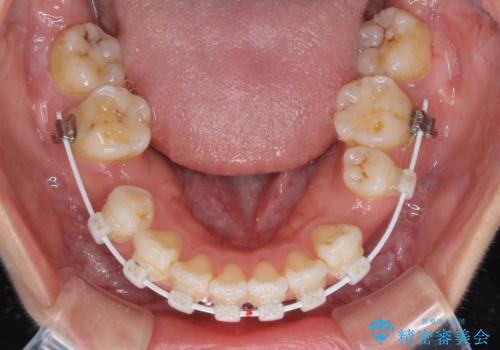

- 審美装置

- 1年11ヶ月

当初はインビザラインによる矯正治療をご希望でしたが、正中を合わせたいことや、口元の突出感を改善したいことから、ワイヤー矯正を強く推奨しました。